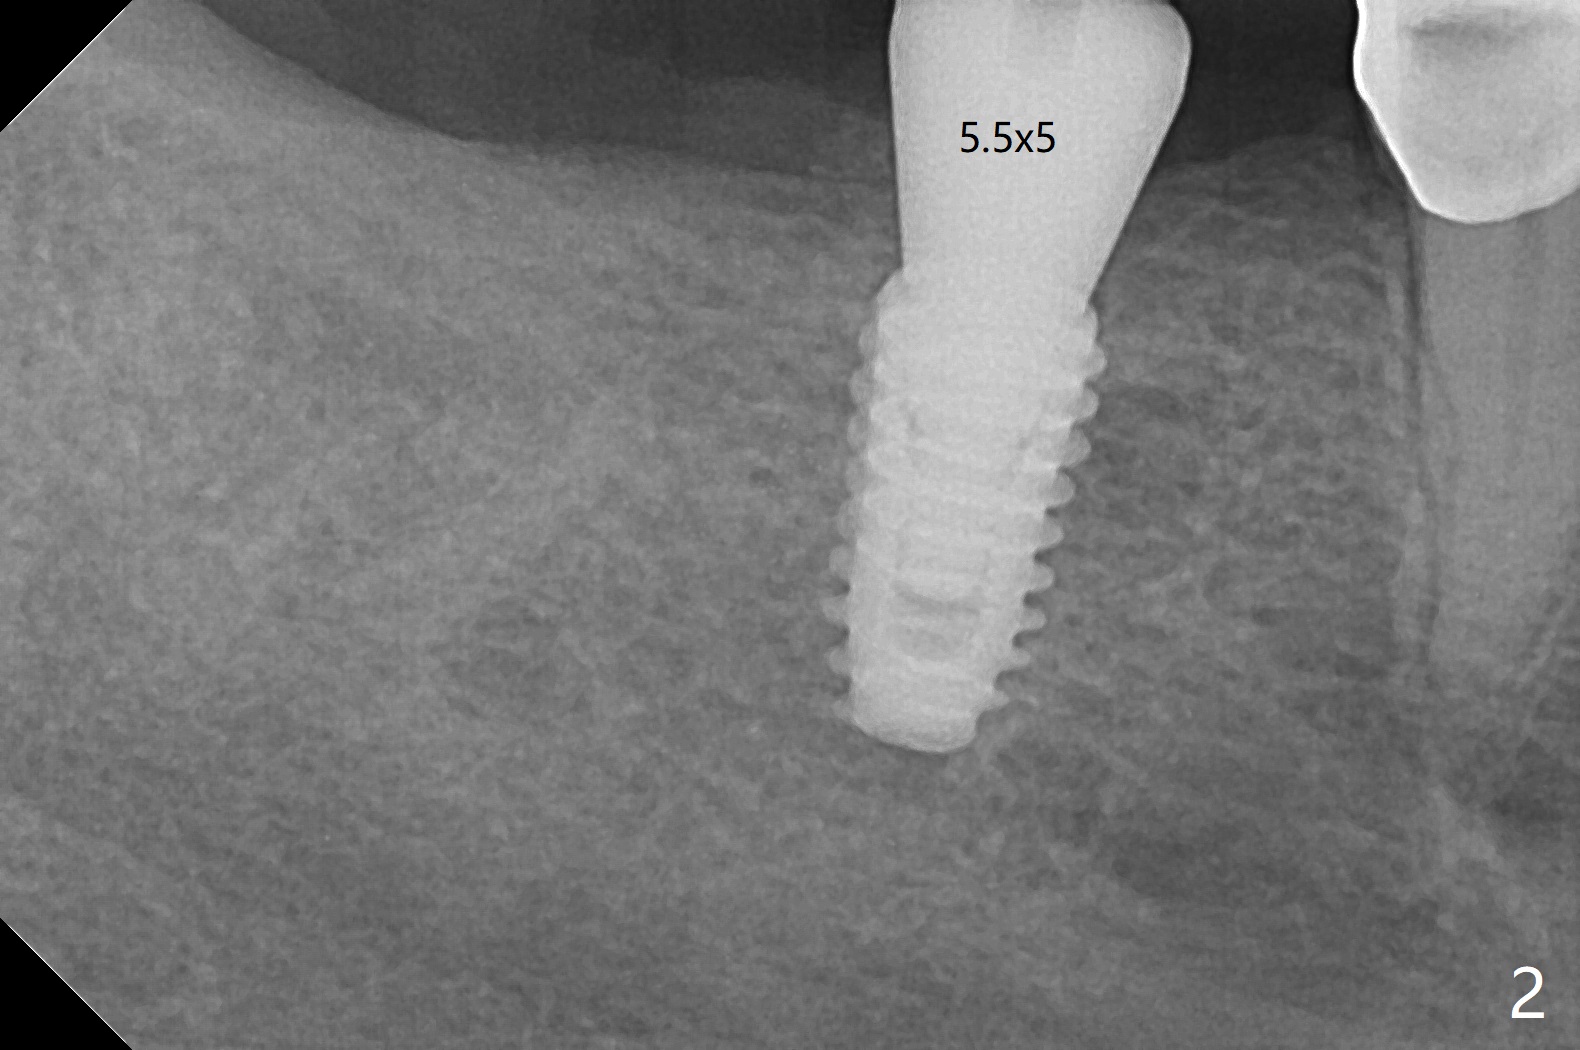

When the guide is seated for #30 implant, it appears that the tissue punch may remove all of the buccal keratinized gingiva. Therefore incision is made with flap reflection. The bigger advantage of flap surgery is that as the implant is placed, the lingual crest is found to be the lowest (which is the most likely to be neglected with flapless approach) so that bone graft can be easily placed. In contrast the mesial crest is the highest. For seating of a cemented abutment (Fig.1) and a healing abutment (Fig.2), profile drills (5.5 and 6.0 mm) have to be used, respectively. Following #31 extraction, Vanilla graft (minor portion) and Osteogen Plug (major portion, most likely no implant in the future) are placed, followed by GEM Cap and 4-0 Chromic Gut suture. After removing the healing abutment 4.5 months postop, a 5.5x4(3) mm cemented abutment is seated completely; it appears that the distal crest resorbs substantially (Fig.3 *). The access hole is distal as related to distal end guide (in fact #31 was used as distal stop before extraction) and radiation interference from #29 crown (Fig.4). The uneven mesial and distal crest may be the main reason for the deviation.